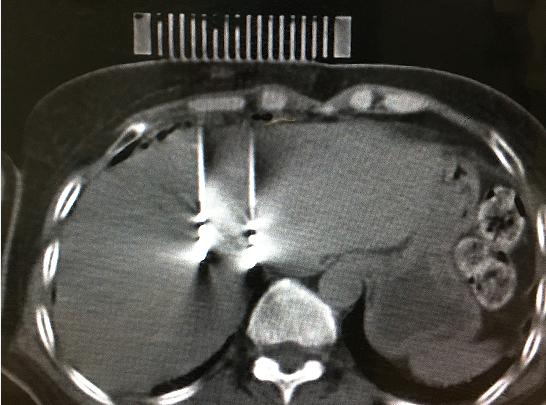

9月11日,醫院腫瘤科張開賢主任醫師團隊對一例肝癌術后復發的患者成功進行了國內首例3D打印共面模板引導下的微波消融術,標志著肝癌進入精準微波消融時代。

患者女性,57歲,肝癌術后5月復發,病灶6.0cmx6.0cm大小,位于肝臟的右葉,靠近隔頂部,經過多學科討論,決定實施經皮微波消融術,由于腫瘤體積較大,需要同時使用兩根消融天線進行多平面消融,為確保療效,兩根消融天線需要平行等距,但由于肝臟是不斷運動的臟器,徒手操作有一定技術難度,往往需要多次穿刺調整進針方向才能達到上述要求,為此,滕州市中心人民醫院腫瘤科張開賢主任醫師團隊借鑒既往采用模板引導放射性粒子植入的經驗,創造性地將3D打印模板技術應用于該例患者的消融治療,在模板引導下在兩個平面上平行等距插入兩根消融天線,經過18分鐘的消融,腫瘤完全壞死,達到完全消融,患者正在術后康復之中。

3D打印模板引導消融的優點:迅速將腫瘤與模板“固定”,防止因肝臟運動導致的穿刺不確定性;確保兩根消融天線平行等距,使熱場分布更加均勻;一次性穿刺布針成功,避免反復穿刺導致的腫瘤種植性轉移;模板對消融天線起到固定,防止因來回移動導致的消融天線位置的改變。據悉,這是國內首例3D打印模板引導下的肝癌微波消融術,這一技術的推廣應用必將造福更多的腫瘤患者。(腫瘤一科 胡苗苗)